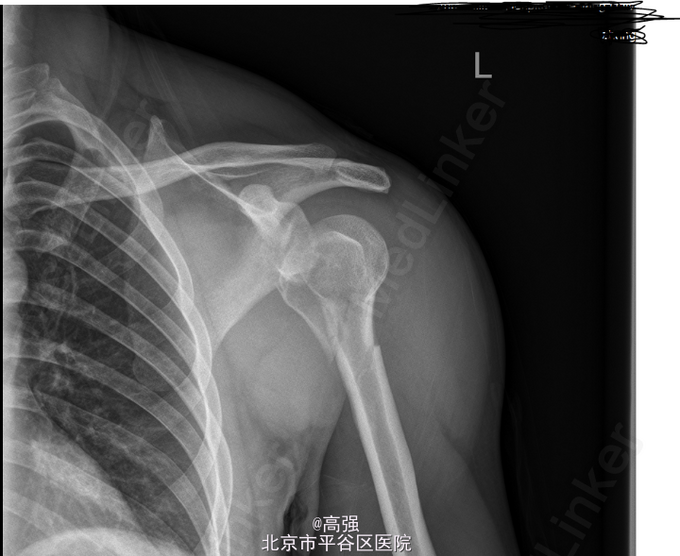

男,39岁。外伤致左肩部肿痛伴活动受限2小时。 患者于2小时前不慎外伤后,当即致左肩部剧烈疼痛,左肩关节活动受限,不能抬举,逐渐肿胀,无恶心呕吐,无其他肢体疼痛不适等,予拍片示“左肱骨近端粉碎性骨折”,为求进一步治疗,来我院就诊,予行X检查后示“左肱骨近端粉碎性骨折”,拟“左肱骨近端骨折”收住入院。

右肩关节疼痛,关节间隙压痛明显,局部肿胀,活动受限,不能抬举,外展,左肩部皮肤完整无破损,左肘关节活动尚可,无明显压痛,左桡动脉搏动可及,末梢诸指活动、感觉可,余肢体无殊。辅助检查:(2015-06-08)本院X线片示:左肱骨近端粉碎性骨折。

初步诊断: 左肱骨近端粉碎性骨折 行左肱骨骨折切复内固定术